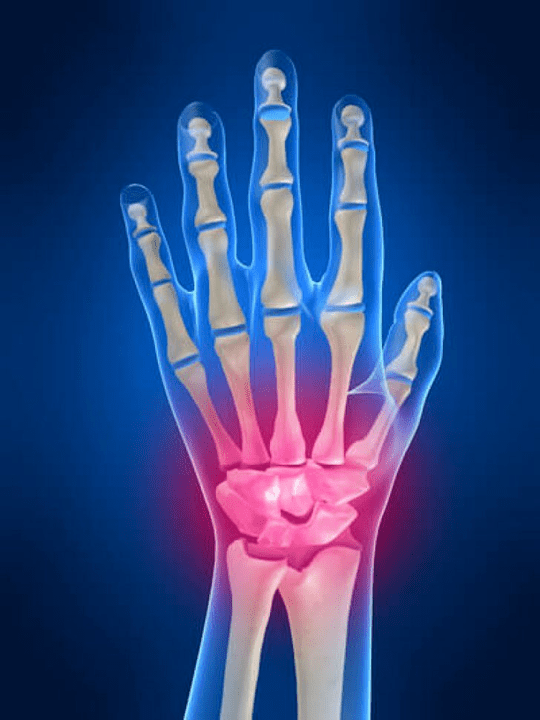

Anatomy of the wrist hands

All hands of arms are common to divide into the following groups:

- Wrist joint;

- wrist joints;

- Carpal sampling compounds;

- Interpencial compounds;

- Parlesemonal-Falan joints;

- Interfalanx compounds.

Wrist joint

Wrist joint forms the bones of proximal bones (upper) numerous wrists (Trihedral, semi -moon, scaphoid bones) and distal areas of radiation and elbow bones.The elbow bone is not directly associated with the bones of the wrist, but with the help of distal (Lower) articulated disk.This structure separates the hollow joint of the joint from the distal cavity (Lower) Tile combination.